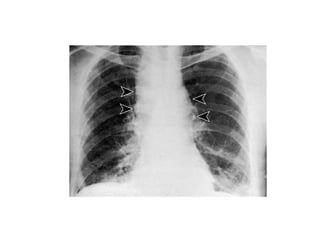

Question 8 27yo with HIV, CD4 ct 175, on daily TMP-SMX Seizure, weeks of stumbling Toxo serology (-) 2 years ago Head CT with 2 large parietal lesions with surrounding edema and midline shift

The best approach to management would be: A.  2 weeks of empiric therapy with TMP-SMX followed by repeat CT B.  2 weeks of empiric TMP-SMX + dexamethasone, followed by CT C.  CT-guided needle biopsy D.  LP to evaluate CSF for EBV PCR E.  Open brain biopsy

Question 8 (CSF for EBV PCR) CT-guided needle biopsy Select the most appropriate management for a patient with HIV and a CNS mass lesion.

Question 8 27yowith HIV, CD4 ct 175, on daily TMP-SMX Seizure, weeks of stumbling Toxo serology (-) 2 years ago Head CT with 2 large parietal lesions with surrounding edema and midline shift

The best approachto management would be: A. 2 weeks of empiric therapy with TMP-SMX followed by repeat CT B. 2 weeks of empiric TMP-SMX + dexamethasone, followed by CT C. CT-guided needle biopsy D. LP to evaluate CSF for EBV PCR E. Open brain biopsy

Question 8 (CSFfor EBV PCR) CT-guided needle biopsy Select the most appropriate management for a patient with HIV and a CNS mass lesion.